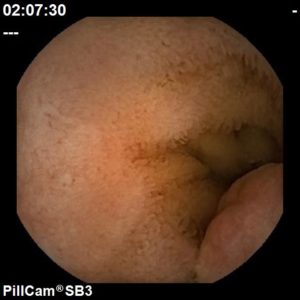

Angiectasia do intestino delgado

Hospital Senhora da Oliveira (Guimarães)